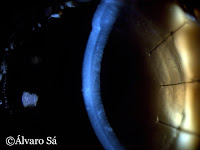

Após instilação de uma gota de corante vital (fluoresceina) observa-se, em toda a superficie ocular, um fino ponteado que corresponde a defeitos epiteliais (ceratite).

Olho esquerdo – Pormenor do ponto lacrimal inferior, através do qual cerca de 85% da lágrima produzida é drenada.

Fotografias tiradas após colocação de um tampão (Plug) no ponto lacrimal inferior, com o objectivo de permitir o contacto da lágrima durante mais tempo com a superficie ocular, através da obstrução, quase total, da sua drenagem. Ultima fotografia mostra o aspecto do olho com Plug colocado (não se observa a olho nú). Coloração amarelada, no canto do olho, corresponde a restos de fluoresceina.